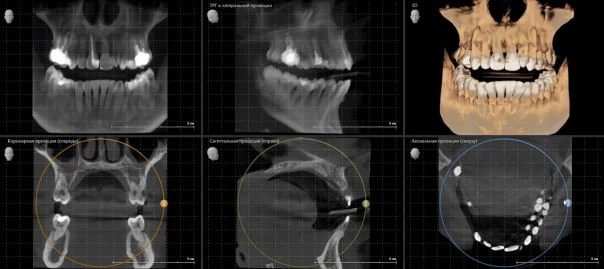

Суть метода заключается в том, что сканер вращается вокруг пациента, посылая узкий пучок рентгеновских лучей. Сенсоры улавливают проходящее излучение, а компьютер преобразует полученные данные в изображение. В отличие от обычного рентгеновского снимка, КТ создаёт трёхмерную модель исследуемой области, что позволяет рассмотреть мельчайшие детали. Особенно ценным это становится при оценке состояния внутренних органов, сосудов, костей, а также при поиске опухолей и очагов воспаления.